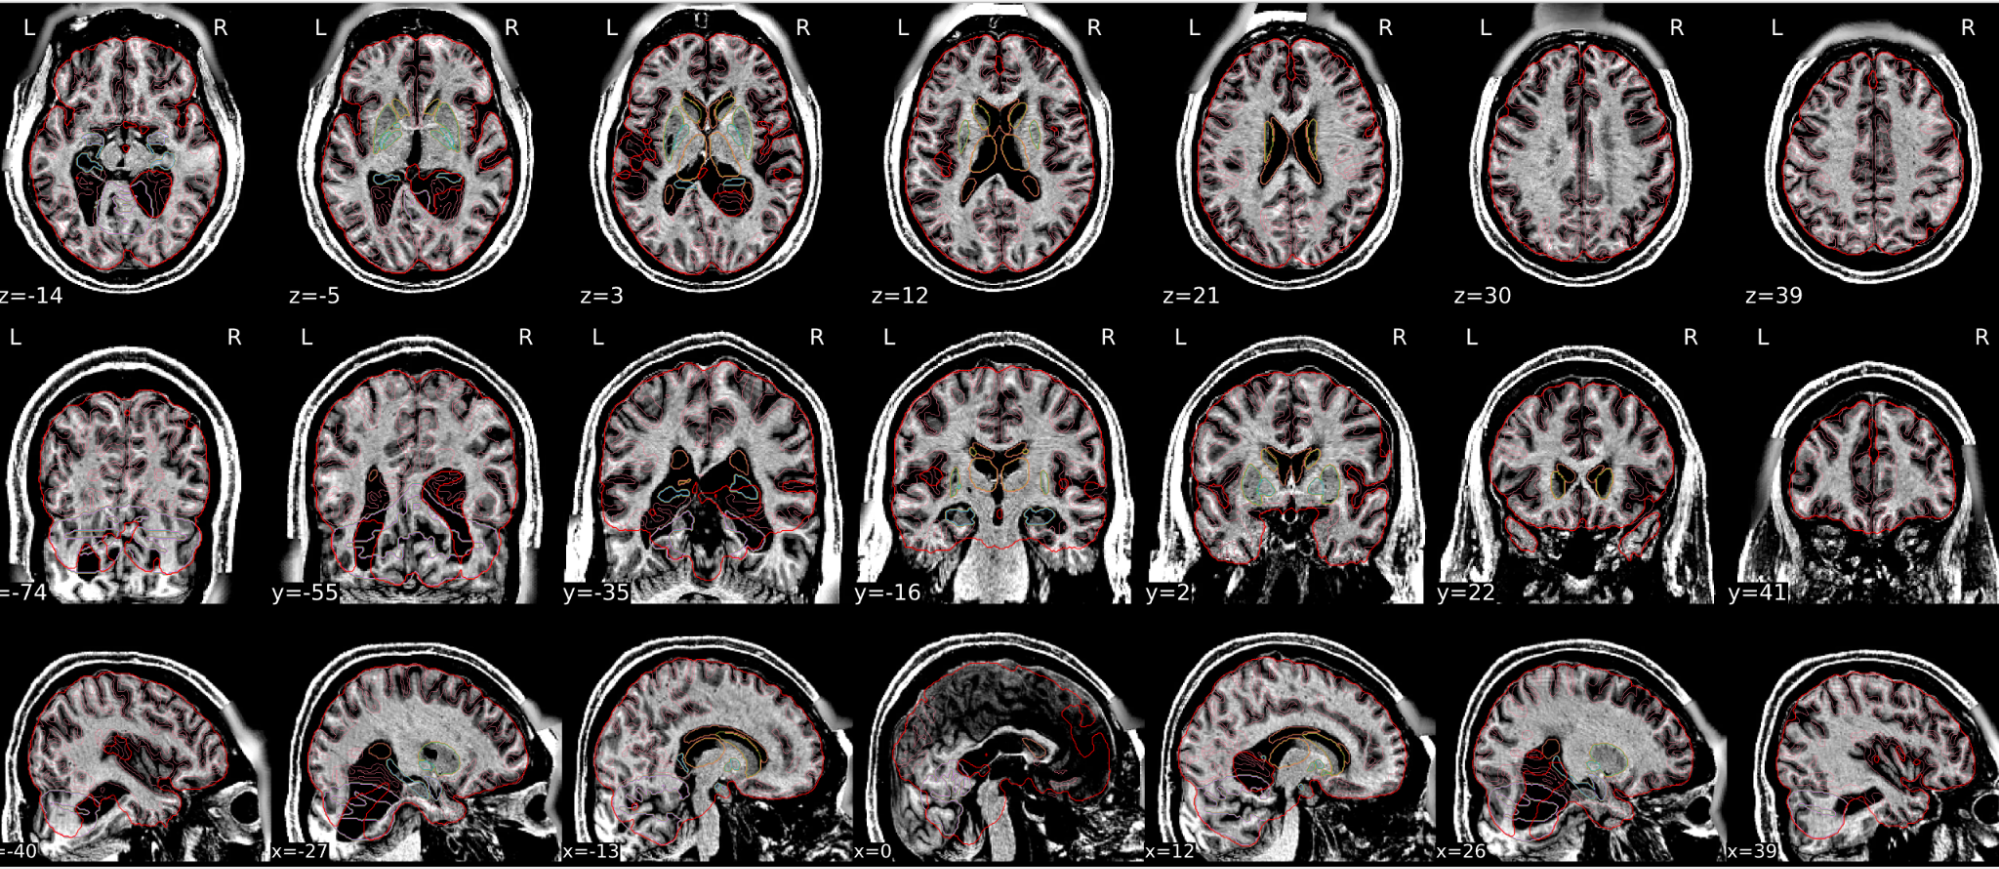

EPI spatial normalisation

This QC step shows the registration of the EPI image to MNI space.

Example of a good subject

- If the registration performed well, you should see an overlap (i.e., correspondence of structures) between the MNI template and the EPI registered to the MNI space.

- If parts of the brain are missing due to the scanner field of view, this is fine. For example, the cerebellum may be cut off for a participant with a large head.

Example of a bad subject

- In case of poor registration, you should see a misalignment of the EPI and the MNI template

Summary

| good | bad |

|---|---|

| Overlap (i.e. match of structures) between the MNI template and the EPI registered in the MNI space | Misalignment of the EPI and the MNI template |

| If parts of the brain are missing because the field of view of the scanner is limited, the EPI spatial normalisation does not have to be excluded e.g. cerebellum cut off in person with large head |

If parts of the brain are missing because the field of view of the scanner is limited, the EPI spatial normalisation does not have to be excluded (e.g. cerebellum cut off in person with large head)